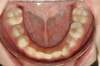

Cas 2 : Description

Tendance prognathisme.Traitement par gouttières.

Avant

Après